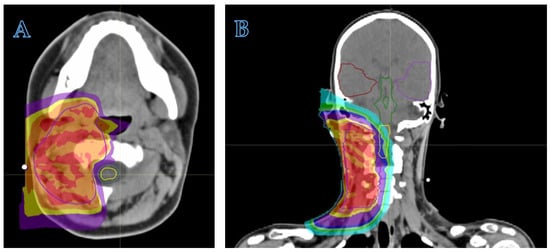

- The anatomical site and the subsequent fragility of the surrounding organs at risk to potential radiation damage is a critical matter. The head–neck, craniofacial, intra-abdominal, pelvic, and paravertebral regions may be considered elective sites, where PBT can minimize radiation exposure to nearby organs (Figure 2). In addition to minimizing the risk of late sequelae, the reduced irradiation of surrounding tissues (mucosae, for example) may also reduce acute toxicity and thus improve compliance with intensive multimodal treatment including concomitant chemotherapy. While PBT may be less indicated for extremity tumors, exceptions should be made for young patients due to the potential for preserving growth plate cartilage and the lymphatic and vascular–nerve pathways present in the limbs.